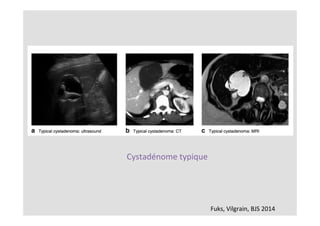

Bilan	morphologique

Scanner

IRM	si	doute	avec	cystadénome

Fuks,	Vilgrain,	BJS	2014

Cystadénome	typique